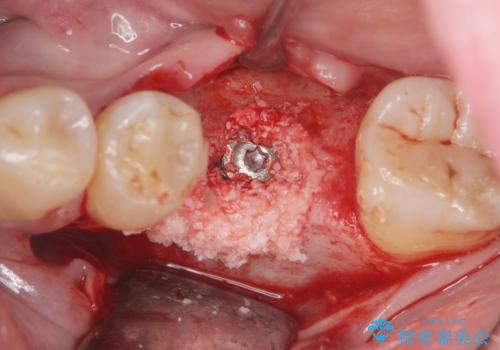

- 歯を破折により失い、インプラント治療を希望され来院されました。

インプラントを埋入し咬合機能を回復するとともに周囲の骨造成も同時に行っていきます。

インプラントを適切な位置に埋入することで、清掃性が高くしっかりと咬合力に耐えられるようなインプラント治療を行うことができます。